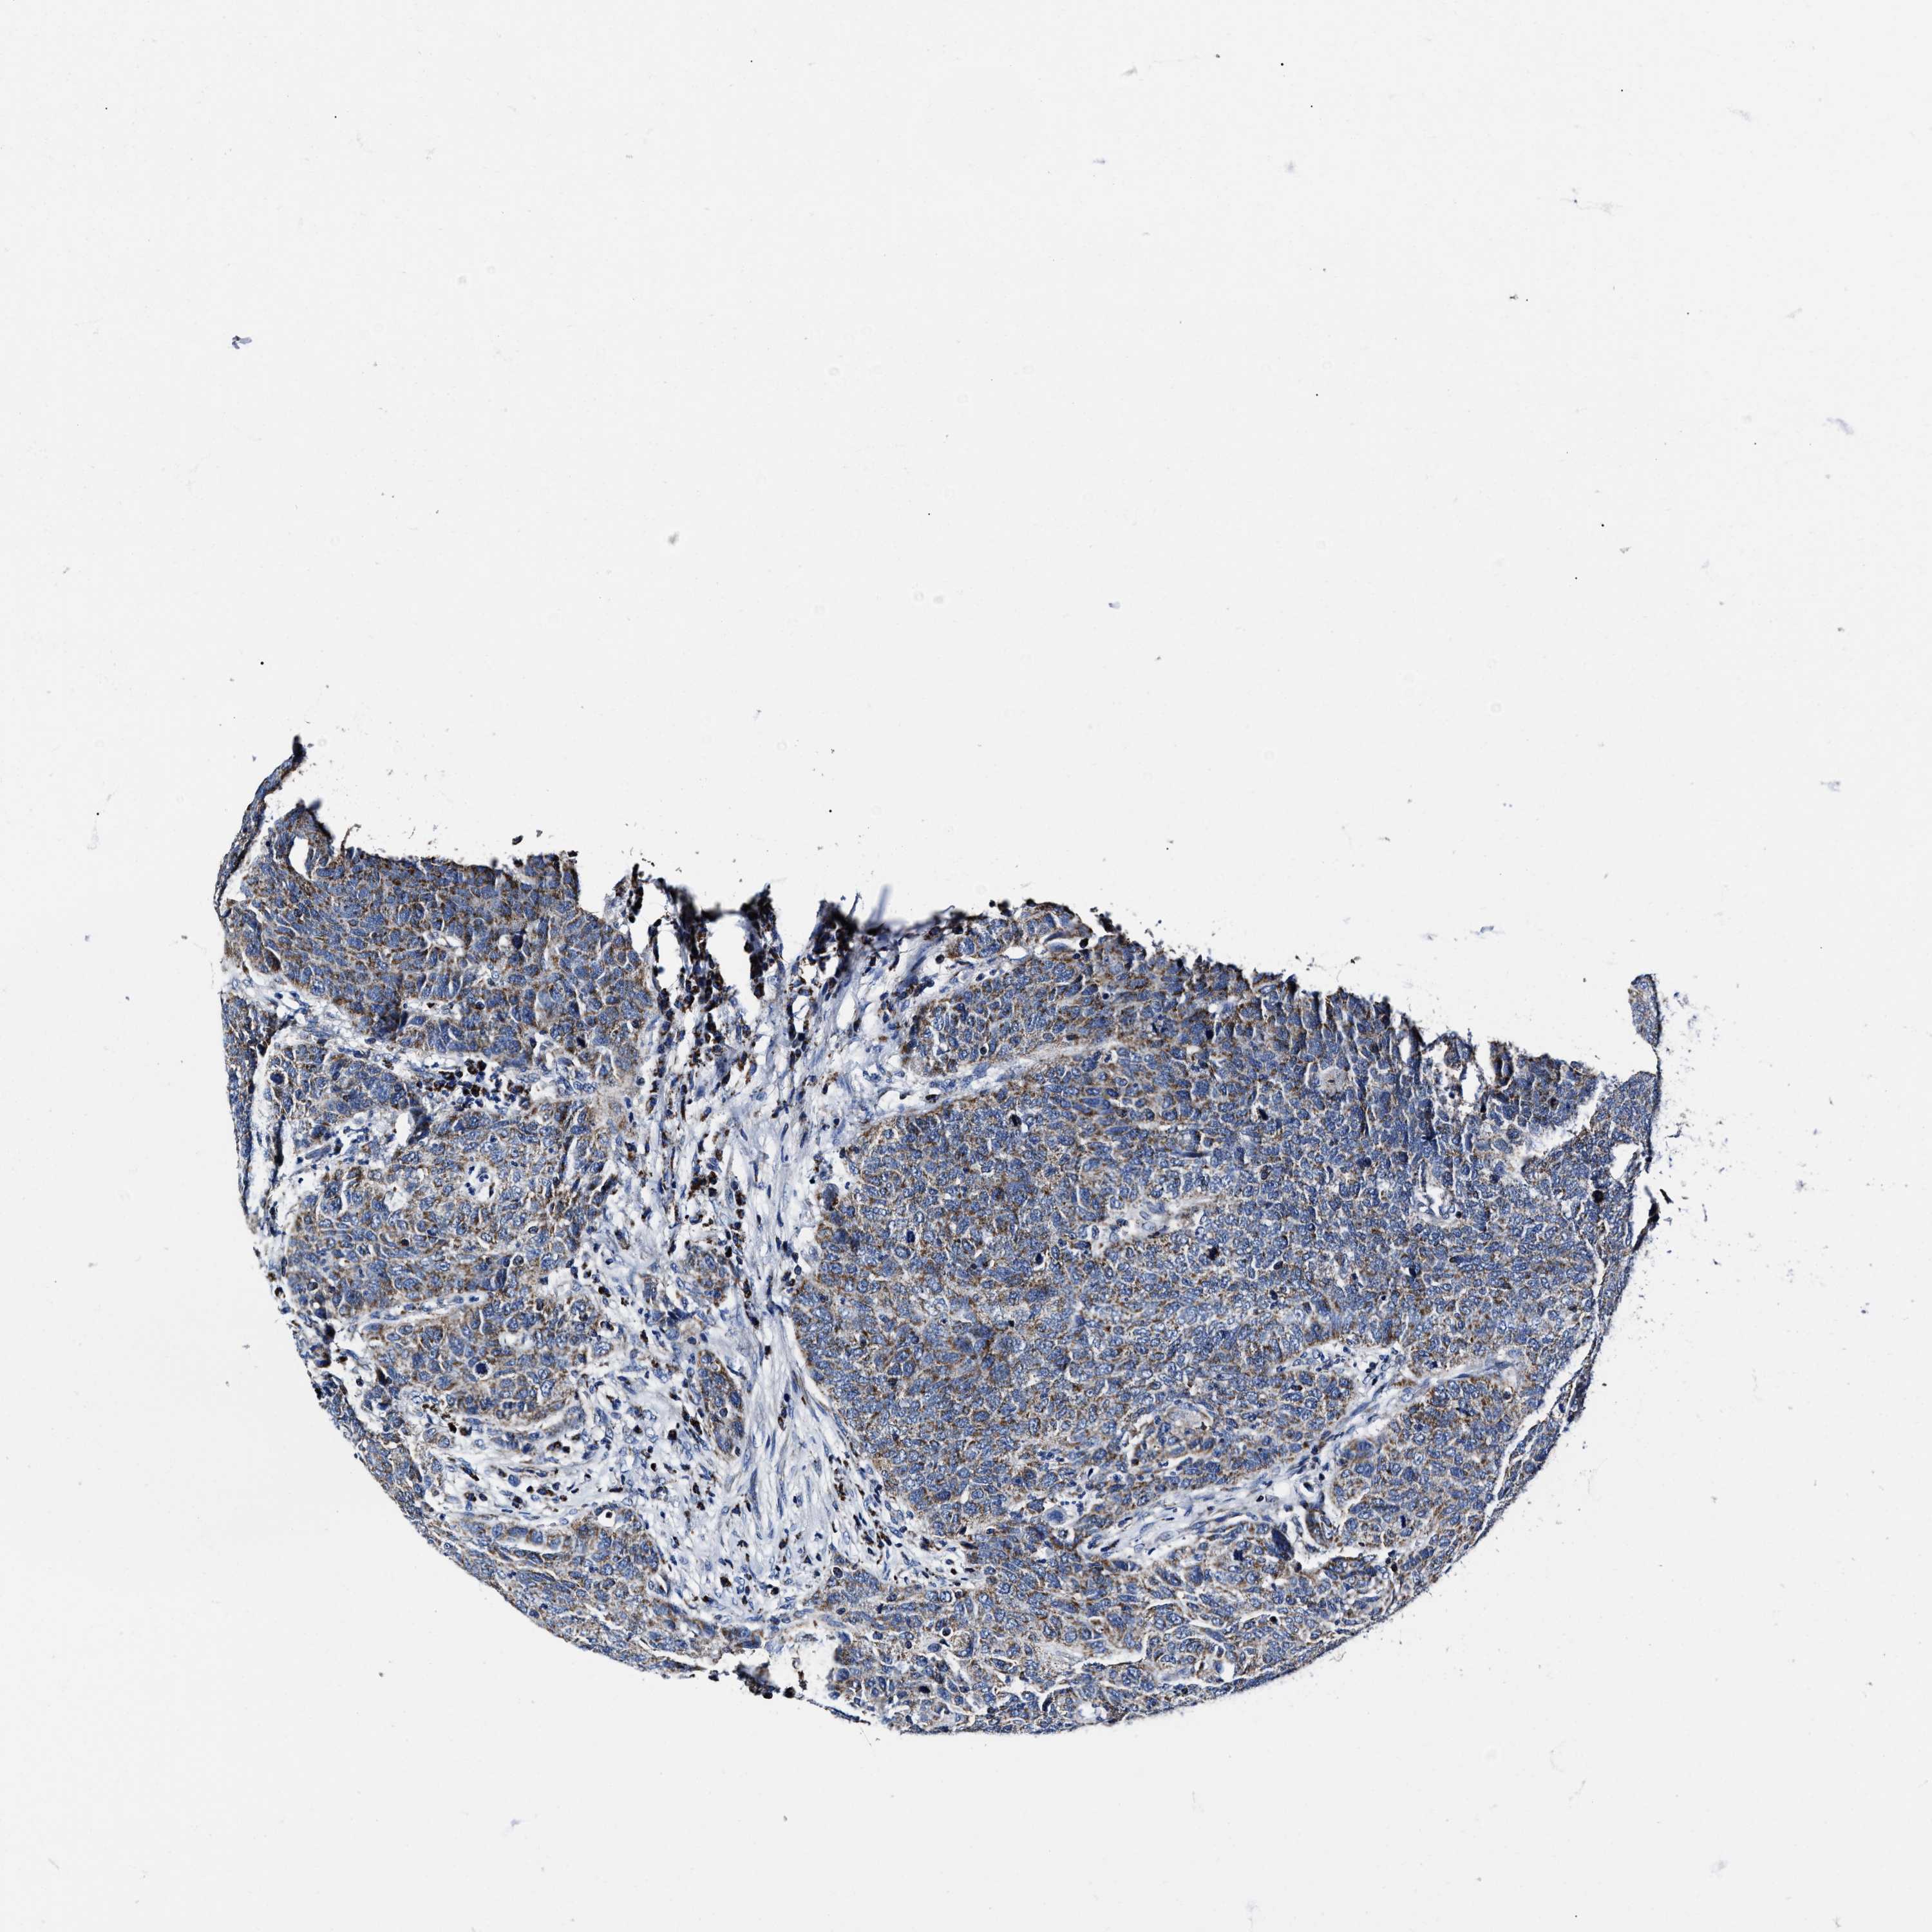

HEAD AND NECK CANCER - Protein expressioni

A mouse-over function shows sample information and annotation data. Click on an image to view it in a full screen mode. Samples can be filtered based on level of antibody staining by selecting one or several of the following categories: high, medium, low and not detected. The assay and annotation is described here.

Antibody stainingi

Antibody staining in the annotated cell types in the current human tissue is reported as not detected, low, medium, or high, based on conventional immunohistochemistry profiling in selected tissues. This score is based on the combination of the staining intensity and fraction of stained cells.

Each image is clickable and will lead to virtual microscopy that enables deeper exploration of all samples and also displays staining intensity scores, fraction scores and subcellular localization as well as patient and tissue information for each sample.

Antibody HPA020961

Staining

High

Medium

Low

Not detected

Intensity

Strong

Moderate

Weak

Negative

Quantity

>75%

75%-25%

<25%

None

Location

Nuclear

Cytoplasmic/membranous

Cytoplasmic/membranous,nuclear

Squamous cell carcinoma, NOS

Squamous cell carcinoma, metastatic, NOS

Adenocarcinoma, NOS